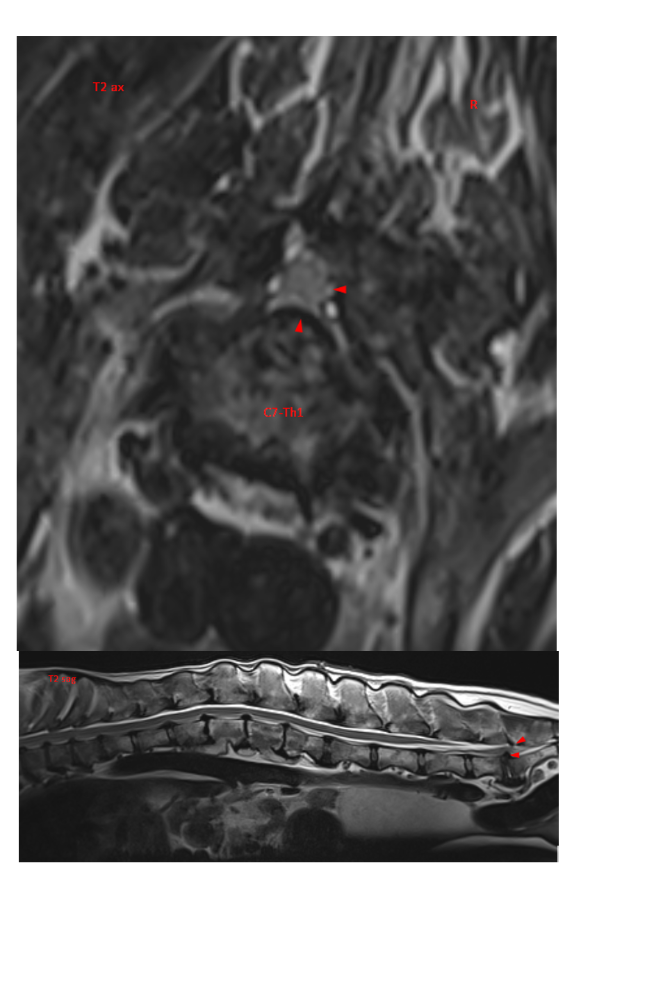

Mosfilmka & Remy Опубликовано 12 мая, 2022 Опубликовано 12 мая, 2022 (изменено) К сожалению, хороших новостей у нас нет... Мы сделали МРТ, результат ниже. Простынь перечисленных проблем... С этим мы пошли к Курганской, уже без Гуру, потому что мотать его туда-сюда снова и трясти в машине ну совсем уже не хотелось. Итог - уколы нам делать нельзя, позвоночный столб воспален, несмотря на долгую антибиотикотерапию. Делать операцию на проблему зада - вся нагрузка упадет на перед, боимся, он просто этого не выдержит. И после этой операции последует операция на перед как заживет зад... Сменили антибиотик по назначению доктора. В общем, все очень печально, ребенок не может сам ходить, лапы отказывают... Дела делает с поддержкой. ?Арине и Сергею низкий поклон за заботу о старичке!! Вспоминаю Старочку и понимаю - как это - ухаживать за собакой, которая постепенно обездвиживается... Баланс 35 141₽ Пополнения: 200руб Лада-Ладушка 3100руб ВИКТОРИЯ 2000руб Печатный экспресс 1300руб пенсия апрель 10000руб пенсия май Итого пополнения: 16600руб Расходы: 528руб аптека 10000руб зоотакси туда-обратно 18500руб МРТ 3500руб прием Курганской Итого расходы: 32528руб ИТОГО БАЛАНС: 19 213₽ Изменено 12 мая, 2022 пользователем Mosfilmka & Remy 3